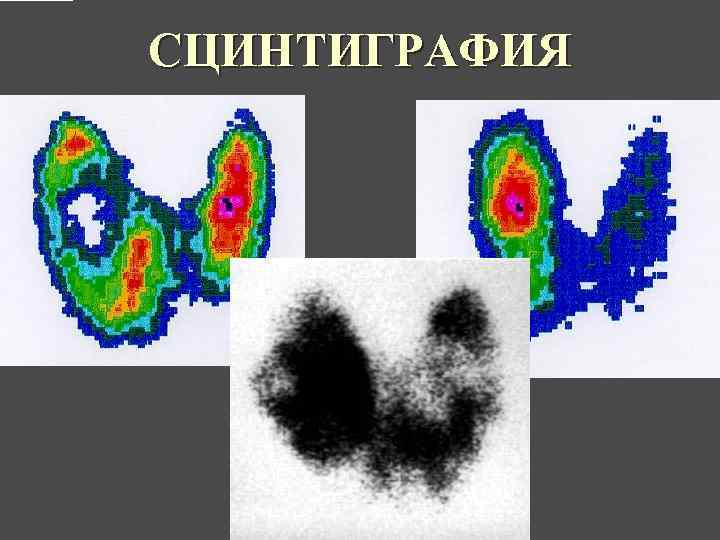

МЕТОДЫ ИССЛЕДОВАНИЯ МОРФОЛОГИИ ЩИТОВИДНОЙ ЖЕЛЕЗЫ Пальпация 2. УЗИ 1. 3. ПТАБ – пункционная тонкоигольная аспирационная биопсия 4. Рентгенография Сцинтиграфия с I 131 6. Компьютерная томография 7. Магнитнорезонансная томография 5.

СЦИНТИГРАФИЯ